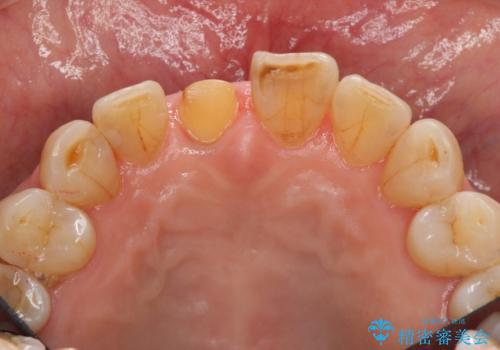

- 前歯を転倒で受傷し、審美性の回復を求めて来院されました。

近医で暫間的なコンポジットレジン修復が為されていましたが、色調に不満があるということでした。

色調の変化が少なく、長期的な予後を見込めるジルコニアクラウンで天然歯を模した審美性の回復を計画します。